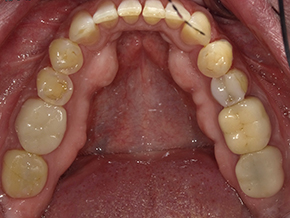

This patient is very happy with his great SureSmile® results, and we are just as happy!